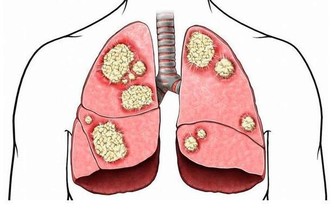

第二位,多種感染

感染是一種常見的並發症,舉例子來說,腹膜透析的患者容易發生腹膜感染,這是極其危險的。還有呼吸道、消化道感染等,都會給腎友們的生命帶來很大威脅。